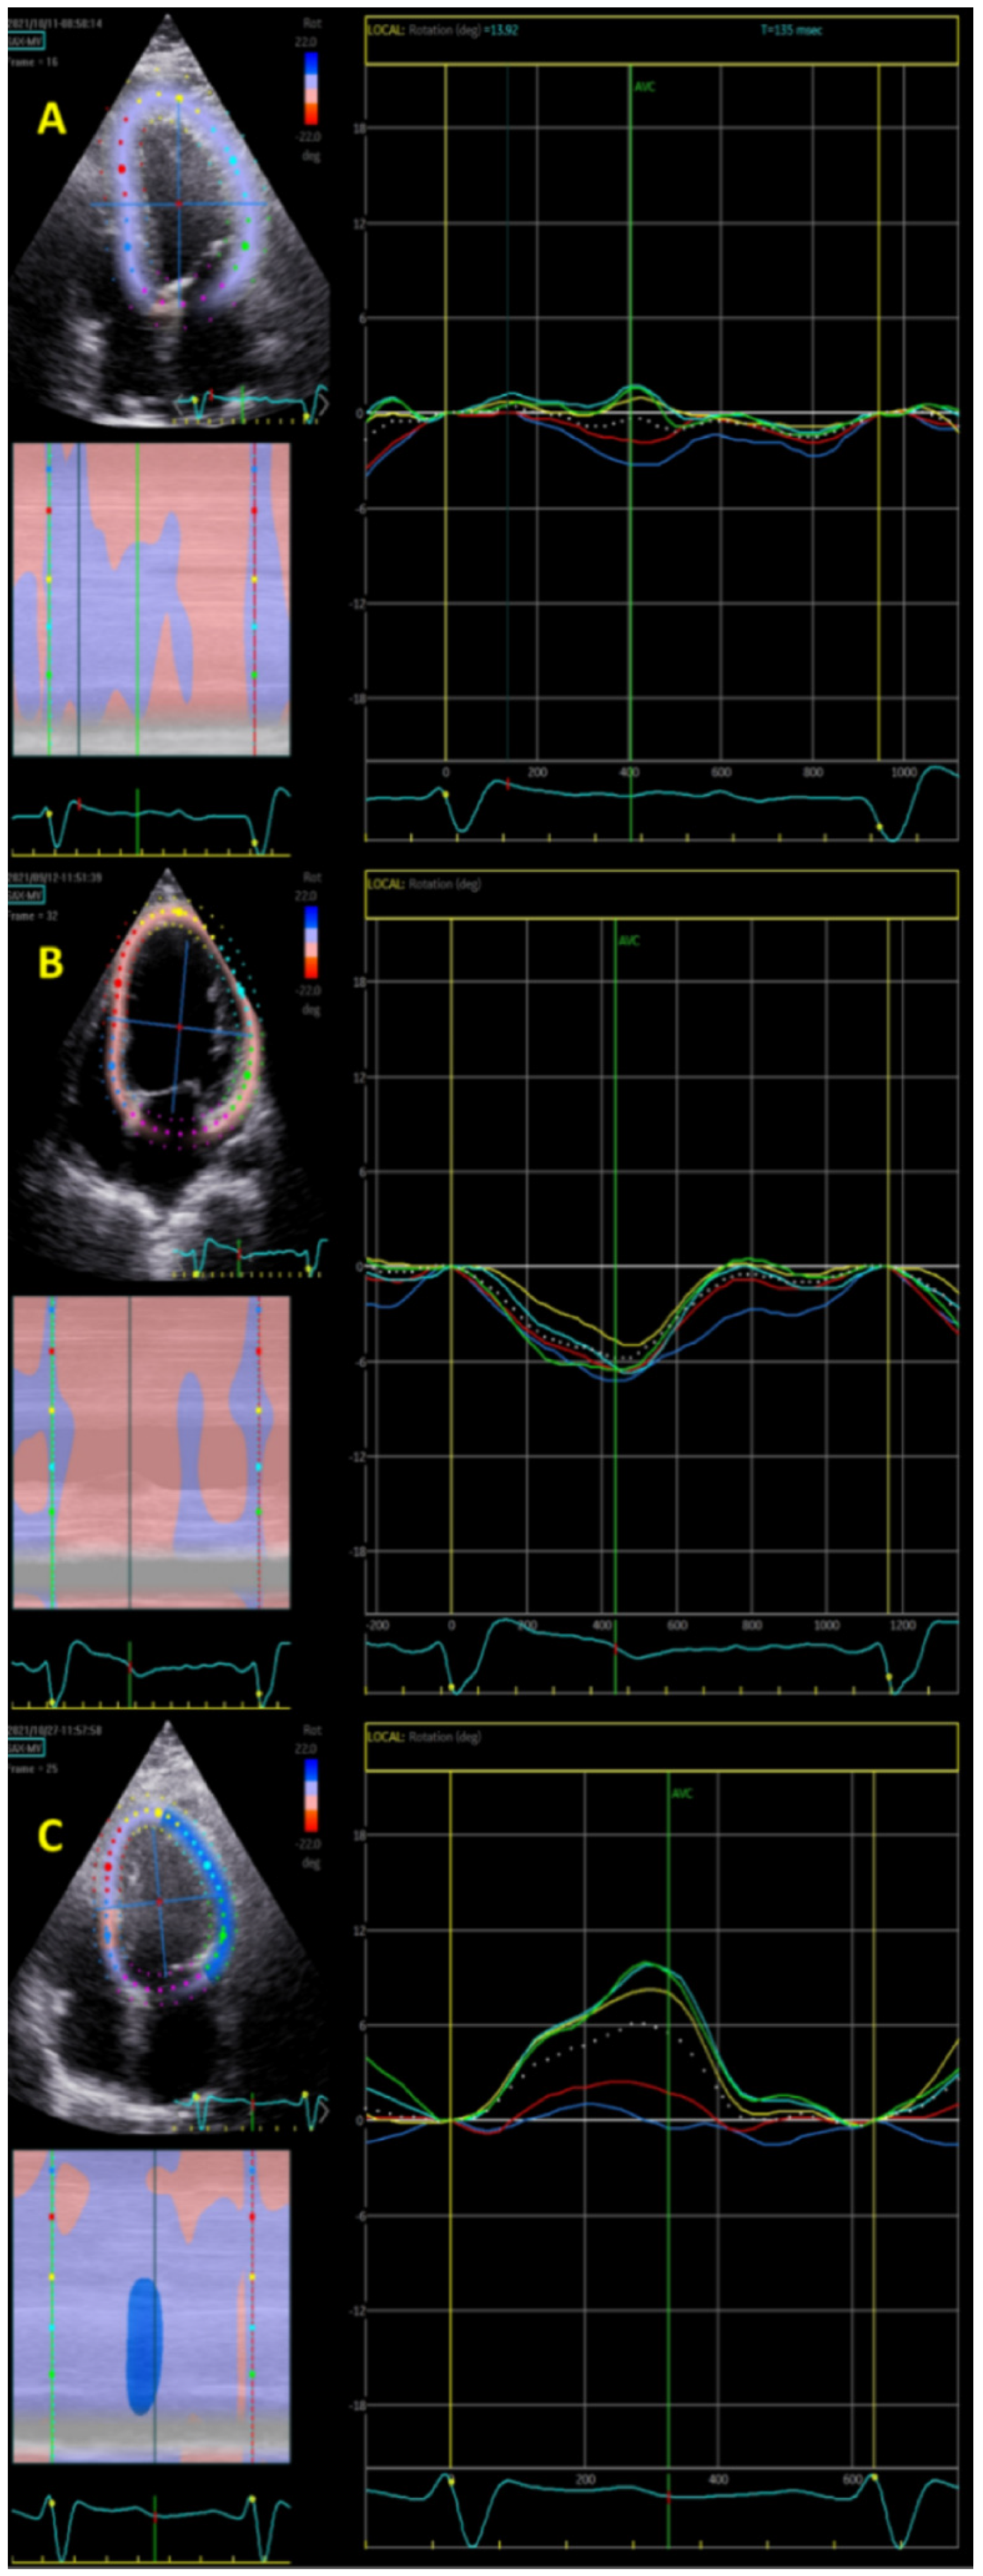

2.3. Longitudinal Rotation Quantification

3.2. Longitudinal Rotation

4.1. Main Findings

4.2. Longitudinal Rotation